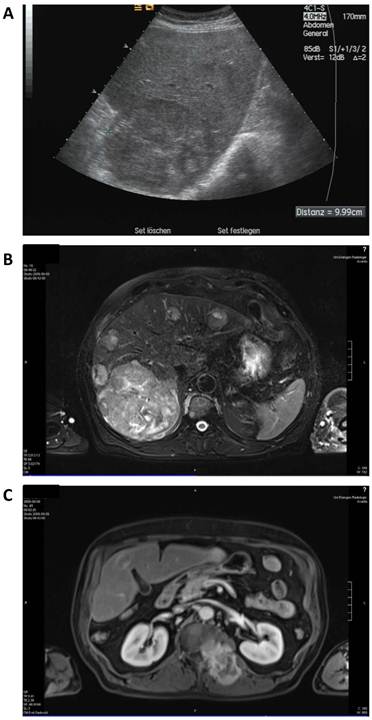

Therapy with sorafenib at 800 mg per day was started in September 2009 and showed a mixed response in MRI scan 6 weeks after treatment start with partly necrotic or decreased lesions but also increasing and novel lesions in the liver and stable soft tissue and bone metastases. Sonography revealed a large lesion (11 cm) in the right liver lobe which was more than 75% necrotic but also 8 additional lesions up to 5 cm (Figure 3).

Figure 3

Staging after sorafenib monotherapy and before initiation of additional panobinostat treatment. A: Contrast enhanced (left) and native sonography (right) showing necrosis (> 75%) in the largest lesion. B: MRI scan of the liver showing a mixed radiologic response compared to baseline. C: MRI scan of the soft tissue metastasis.